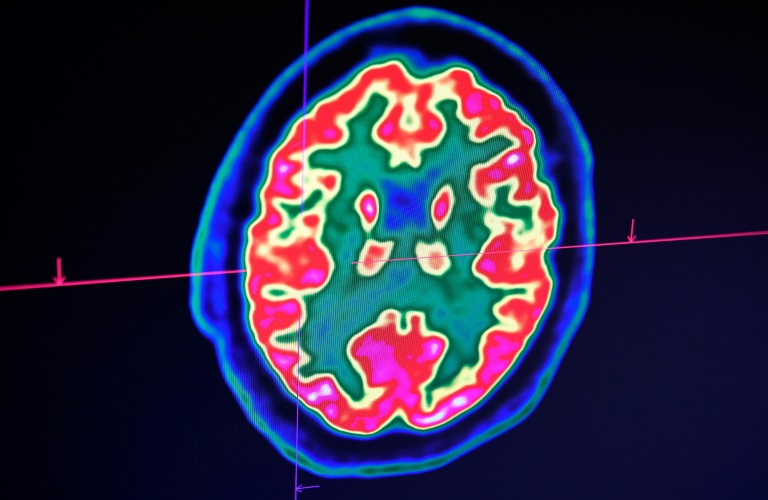

Ảnh chụp não người bằng máy chụp cắt lớp positron (PET). Ảnh: AFP.